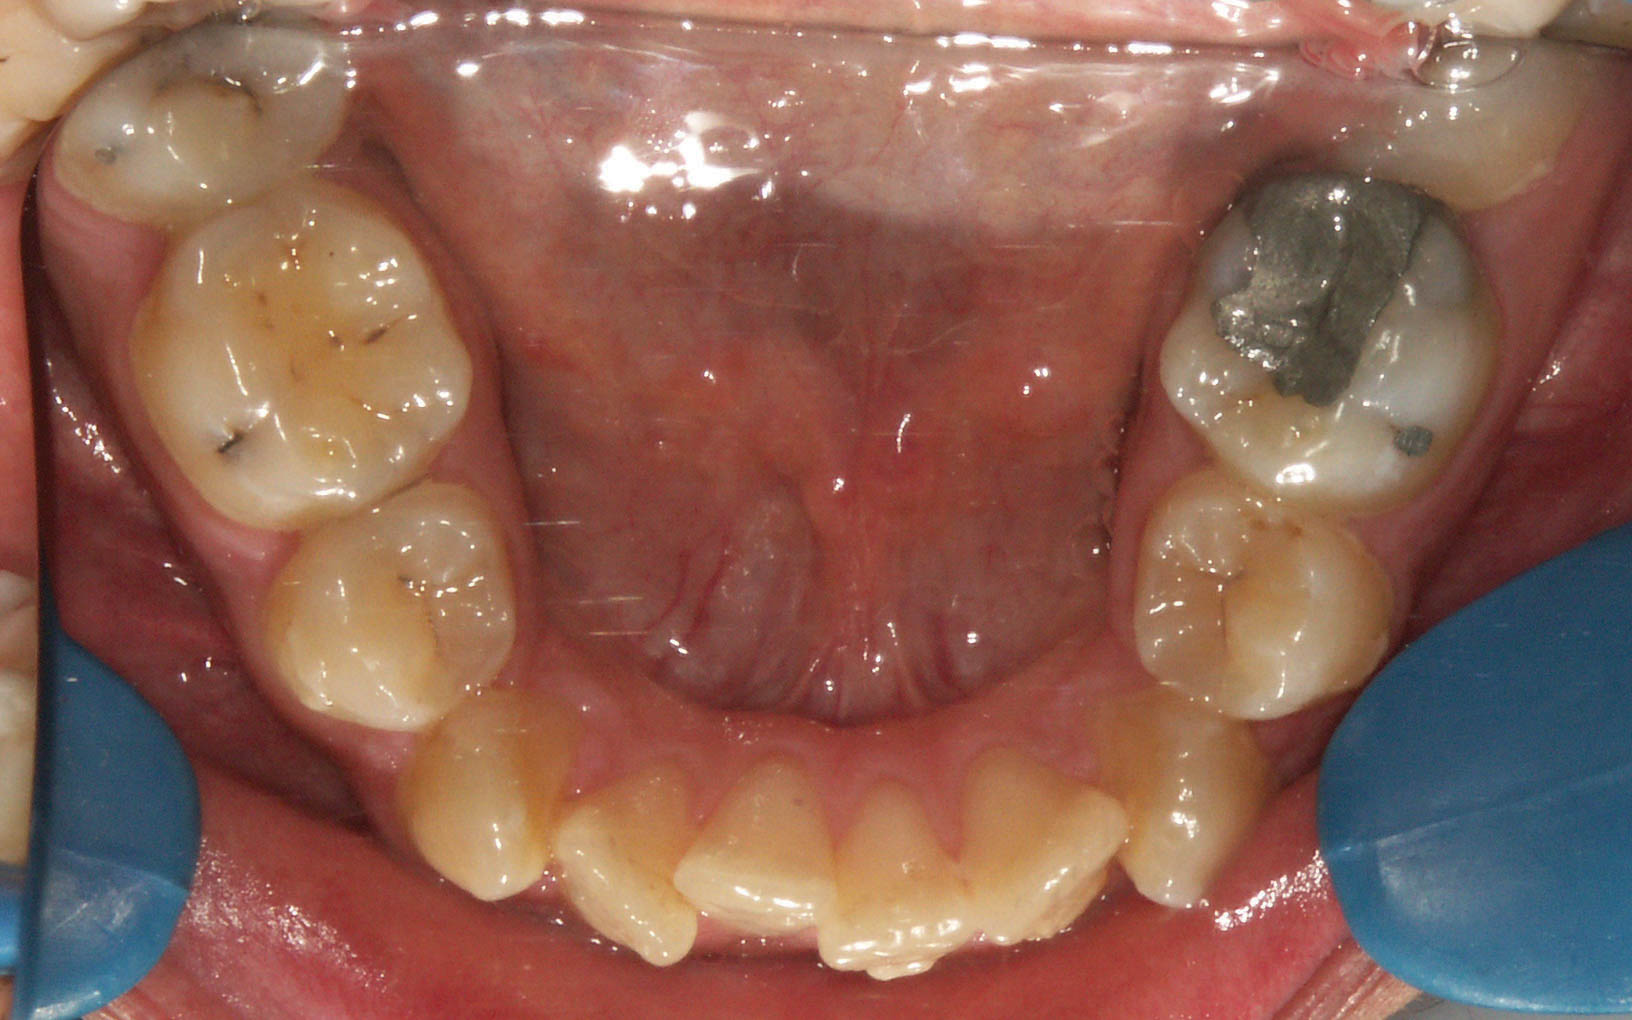

اصولاً در هر سمت بیشتر از یک دندان نمیتوان کشید. بیمارانی را میبینیم که فرضاً درمان Serial Extraction غلط شدهاند و فضای پرمولرهای کشیده شده از بین رفته اما هنوز کرادینگ دارند (شکل 201-1) یا به هر علت دیگری در هر سمت یک پرمولر را از دست دادهاند و کرادینگهای زیادی هنوز مانده است (در بیماران high angle فضای کشیده شده قبل از رفع کرادینگ بخاطر حرکت مزیالی سریع مولرها بسته میشود). دیگر نمیتوانید دندان دیگری بکشید. اگر كمبود فضا زیاد باشد میتوان دندانهای 6 تا 6 را استریپ كرد و در هر طرف 4mm فضا بدست آورد.

شکل 201-1: کمبود فضا بیشتر از کشیدن یک پرمولر